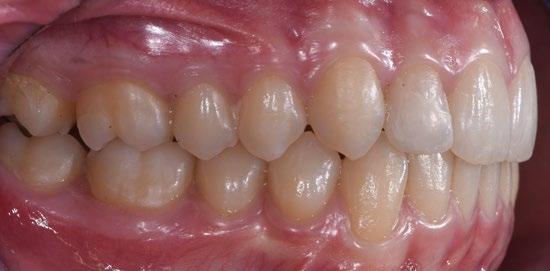

Paciente mujer de 35 años, con amplia exposición gingival en sonrisa y alta demanda estética (Fig. 1, 2).

Su solicitud inicial es volver a blanquear el 21, que había sido previamente endodonciado y había recibido sucesivos tratamientos blanqueadores que habían recidivado. Refiere ligera molestia en la papila interincisiva. En la exploración radiográfica intraoral 1 2

En el examen extraoral (Fig. 1), se observa una buena simetría de la línea media dental superior en comparación con la línea media facial, mientras que la inferior muestra una desviación hacia el lado derecho del paciente. Al sonreír, se aprecia una exposición limitada de los incisivos superiores. El perfil es agradable, con un ángulo nasolabial y un ángulo labiomentoniano normales. En el examen intraoral (Fig. 2), en el arco superior, el grado de apiñamiento es leve-mo-

derado, especialmente caracterizado por el canino del hemiarco izquierdo (2.3) en una posición poco erupcionada y vestibular en comparación con los elementos adyacentes, debido a una falta de espacio en el arco. En el hemiarco opuesto, el canino (1.3) tiende hacia una clase dental cabeza a cabeza, con una asimetría resultante en las líneas medias dentales. En el arco inferior, el apiñamiento es

moderado con rotaciones importantes, especialmente en los caninos (3.3 y 4.3) y el incisivo lateral 3.2. Al calcular el índice de Bolton, se observa una discrepancia en las dimensiones mesiodistales de los dientes del arco superior en comparación con los del arco inferior. Específicamente, los incisivos laterales (2.2 y 1.2) tienen ambos una amplitud reducida. En el plano vertical, hay una mordida profunda y una curva de Spee aumentada.